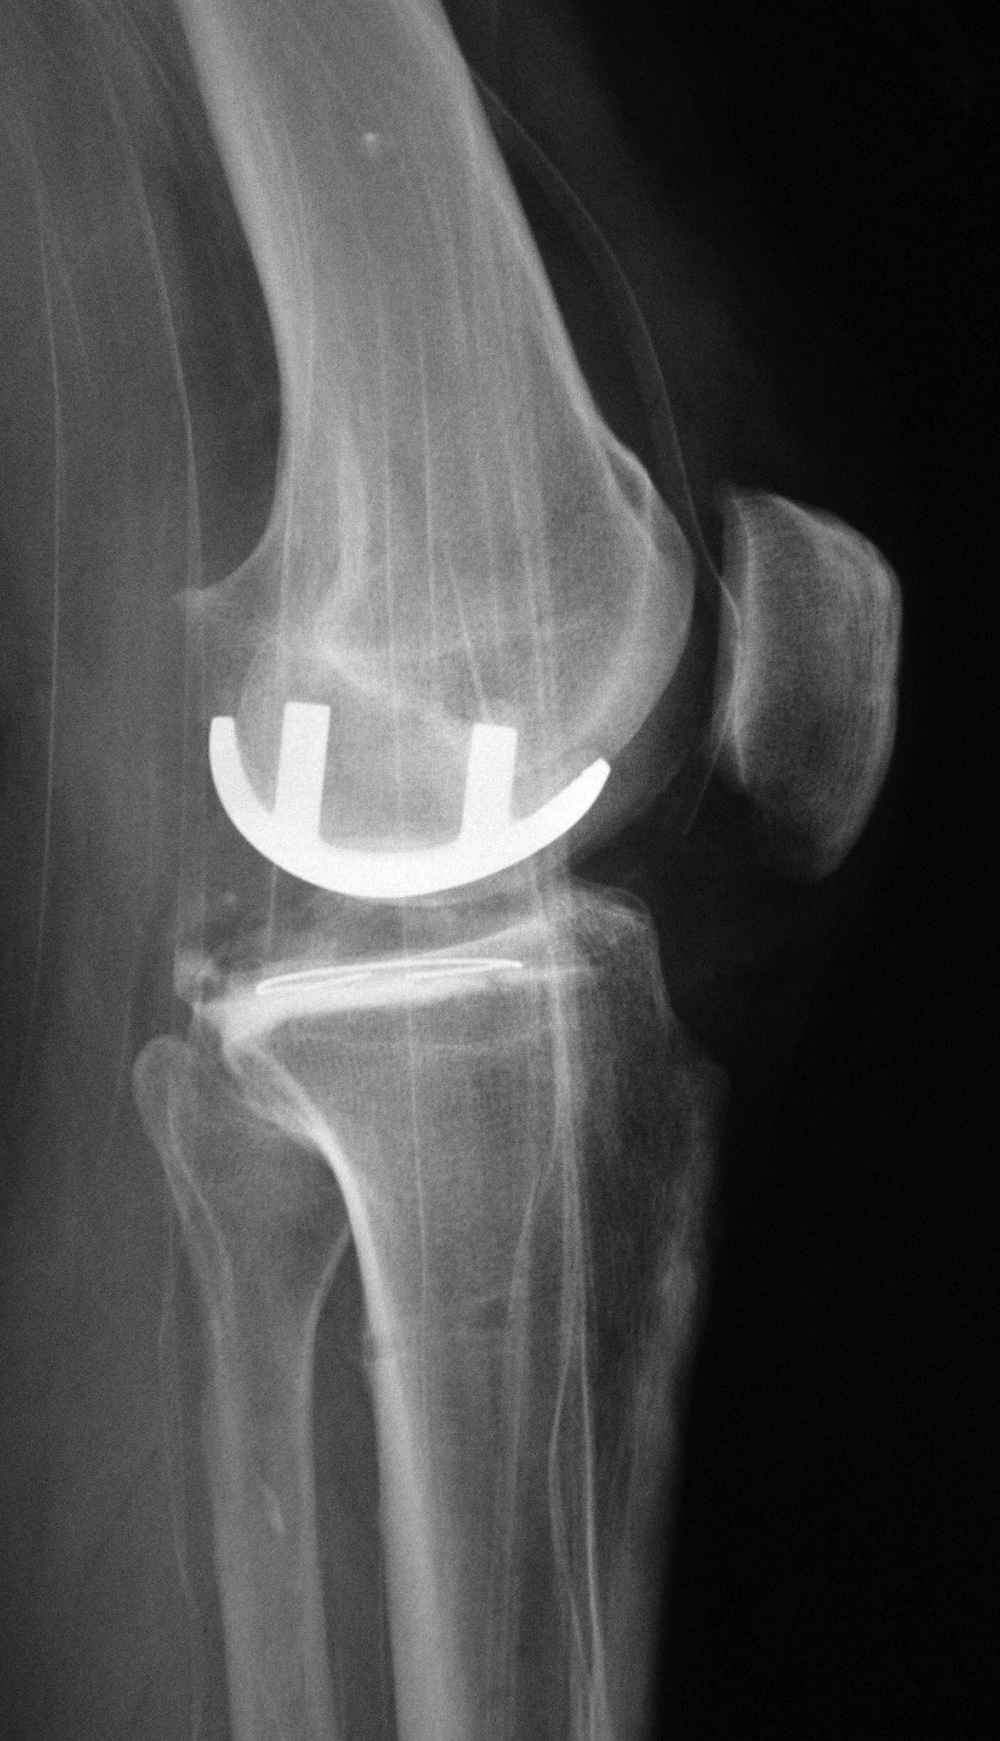

| Posterior cruciate retaining total knee prosthesis with cementless femoral and cemented tibial component and patellar resurfacing |

| There is a postoperative drain and skin staples. From Taljanovic, 2005 |

There is also a surgical drain and skin staples in place. 65 year-old woman. |